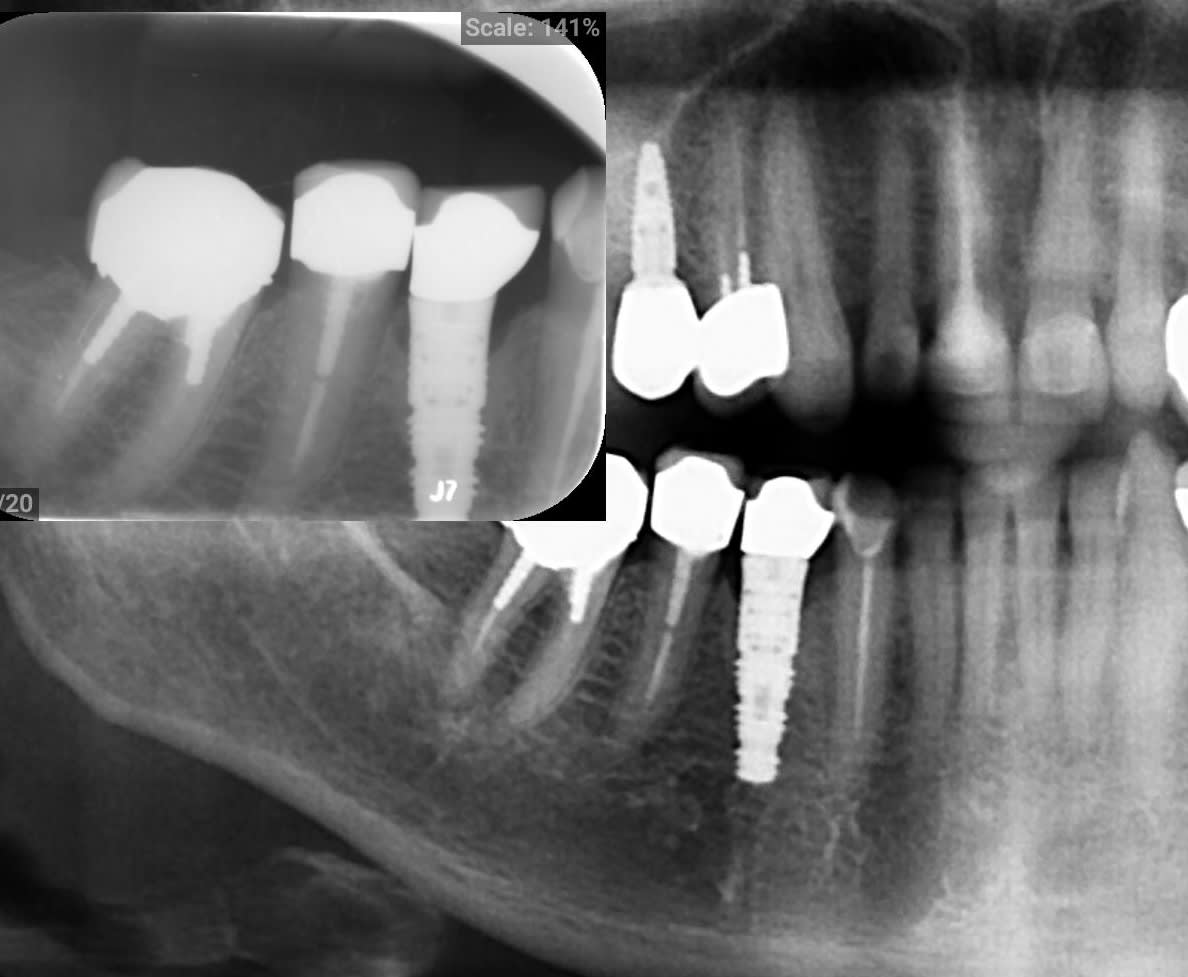

Je cherche une identification implantaire position 44 pour un patiente qui a devissée/descellé la restauration prothtique.

très facile...Frialit 2

mais pour résumer il y a 3 types de tournevis utilisés pour ce système, un plat de 2mm, un hexagonal de 1.22mm (un peu plu petit que du zimmer qui fait 1.25mm...donc en fait plus proche de ceux de chez Anthogyr ou ETK ou Glogal D qui sont en 1.2mm) et un hex de 0.9mm